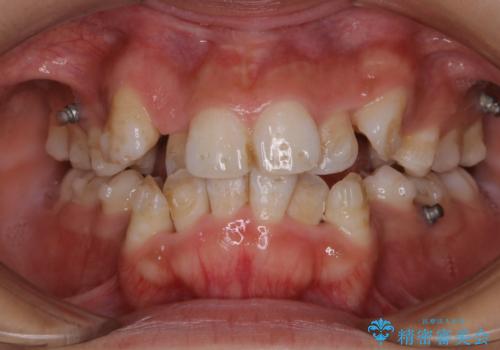

表のワイヤー矯正治療中にPMTCで綺麗に

担当医 歯科衛生士